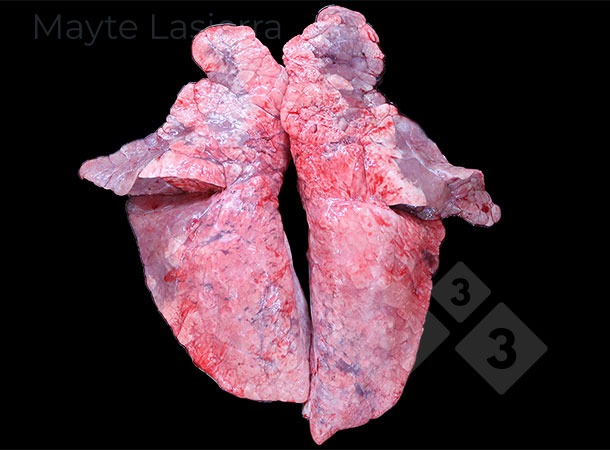

Zapalenie opłucnej występuje często i obejmuje zmiany chorobowe w dogrzbietowo-doogonowej części płuca, związane głównie z podostrą lub przewlekłą postacią zapalenia opłucnej świń (APP). Objawia się białymi plamami na opłucnej trzewnej płatów przeponowych, odpowiadającymi złogom włóknika.

Zapalenie opłucnej może również występować w obszarach doczaszkowych płuc, powodując zrosty między sąsiednimi płatami płucnymi. Zazwyczaj towarzyszą mu koinfecje pochodzenia bakteryjnego (Pasteurella multocida, Glaesserella parasuis, Streptococcus suis itp.) i nazywane są zapaleniem opłucnej doczaszkowej, aby odróżnić je od zapalenia opłucnej związanego z APP.